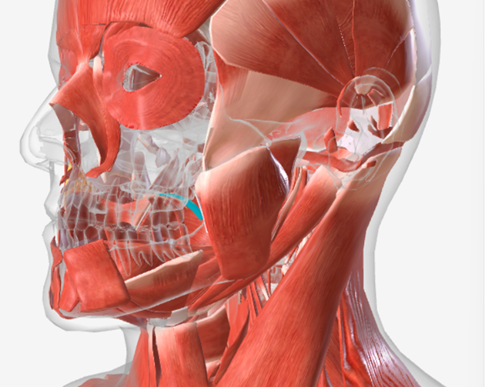

Inferior pharyngeal constrictor

origin is the oblique line of the thyroid laminae, coursing up and back to insert on the median pharyngeal raphe; function is to reduce the diameter of the lower pharynx

Inferior Pharyngeal Constrictor

|  |  |

Inferior pharyngeal constrictor

E

Inferior pharyngeal constrictor

E

Inferior pharyngeal constrictor

H